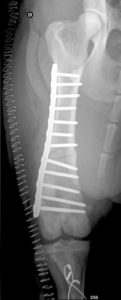

• Correction de la luxation par sulcoplastie trochléaire, transposition crête tibiale et doublement rétinacle

• Correction du varus fémoral, pathologie par ostectomie cunéiforme fermée de 19° de la face latérale

• «Galys» est revue à 30 et 90 jours post-opératoires pour des contrôles cliniques et radiologiques post-opératoires du fémur gauche. L’évolution post-opératoire est favorable et l’appui du membre opéré totalement physiologique à 90 jours post-opératoires

• La rotule droite est centrée sur les clichés post-opératoires

• Le varus pathologique du fémur distal droit est corrigé par l’ostectomie cunéiforme fermée de 15° de la face latérale